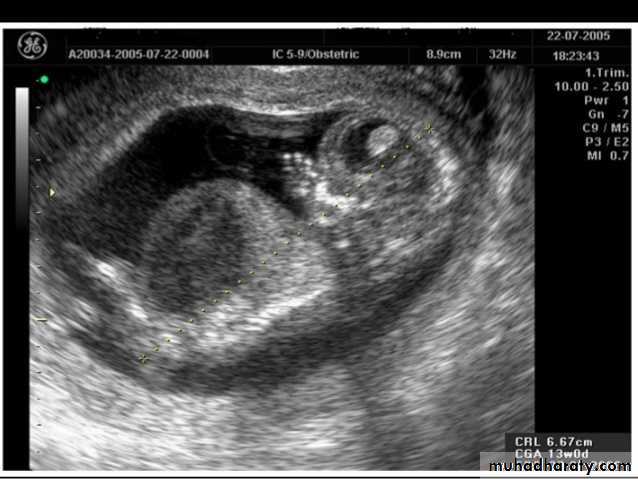

Mosul Medical College /radiology department2016BPD together with head circumference (HC), abdominal circumference (AC), and femur length (FL) are computed to produce an estimate of fetal weight. In the second trimester this may be extrapolated to an estimate of gestational age and an estimated due date (EDD) .